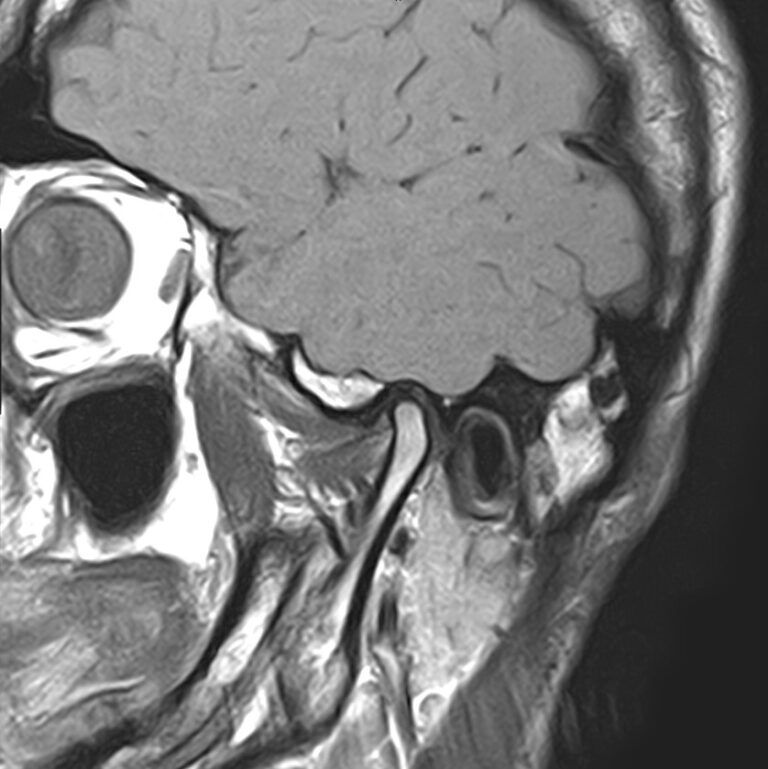

Височно-нижнечелюстной сустав является парным комбинированным суставом и имеет сложное строение. В него входят суставные ямки височной кости, суставные головки нижней челюсти и расположенные между ними хрящевые пластинки – мениски, выполняющие роль амортизаторов.

Чаще всего дисфункция височно-нижнечелюстного сустава обусловлена внутренним повреждением, смещением мениска и суставной головки нижней челюсти. Для определения степени смещения внутрисуставных структур выполняется функциональная проба с проведением МРТ в двух положениях:

Магнитно-резонансная томография является наиболее точным и эффективным методом диагностики поражения височно-нижнечелюстных суставов, так как позволяет получить детальную информацию о состоянии не только костей, но и связочного аппарата, хрящей, менисков, жевательных мышц, окружающих мягких тканей.

В клинике «Доступная медицина» можно пройти исследование МРТ височно-нижнечелюстного сустава на высокотехнологичном оборудовании. Клиника располагает новейшим томографом экспертного класса TOSHIBA VANTAGE TITAN 1,5 Тесла, который благодаря высокой индукции магнитного поля позволяет получать изображения исследуемой зоны в мельчайших подробностях. Томограф производит послойное сканирование области сустава и околосуставных мягких тканей, затем с помощью цифровых приложений преобразует полученные данные в трехмерные изображения превосходного качества.

При проведении магнитно-резонансной томографии на изображениях визуализируются: височная кость, головка мыщелкового отростка нижней челюсти, суставная щель. Помимо костных структур МРТ позволяет оценить состояние мягких тканей – внутрисуставного диска и связочного аппарата височно-нижнечелюстного сустава, жевательных мышц.